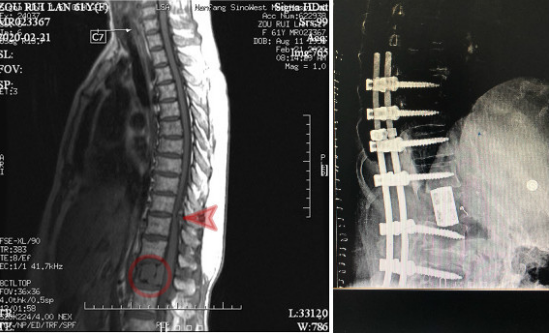

图左:术前MR示腰椎肿瘤(圆圈处)、胸椎狭窄(箭头所指)。

图右:术后X光,病变脊椎切除,代以人工椎体。